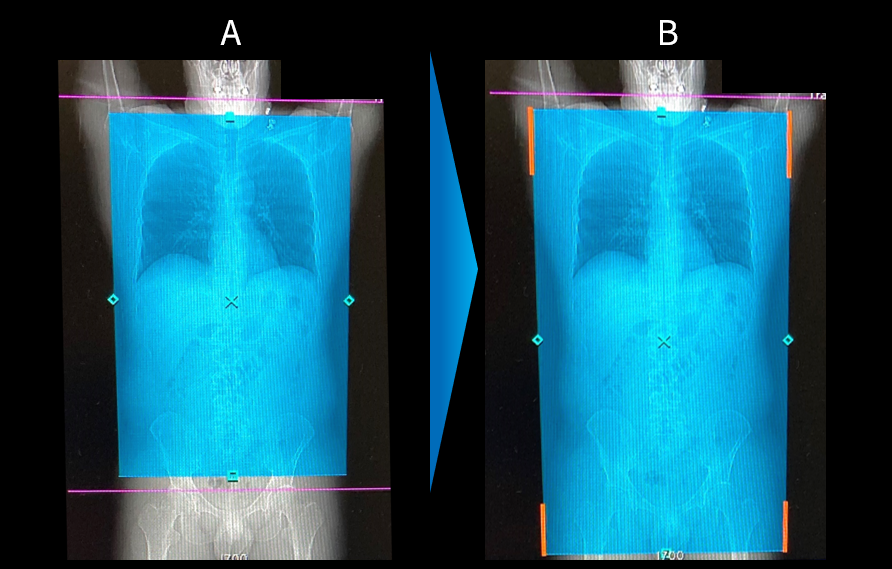

Ascend_Teine_04.png

図3 Smart Planによる肺~骨盤の撮像計画

A:撮像プロトコルに設定してあるデフォルト撮像範囲

B:Smart Planによる推奨撮像範囲

Smart Planにより肺~骨盤までの撮像範囲およびD-FOVが自動で設定されている